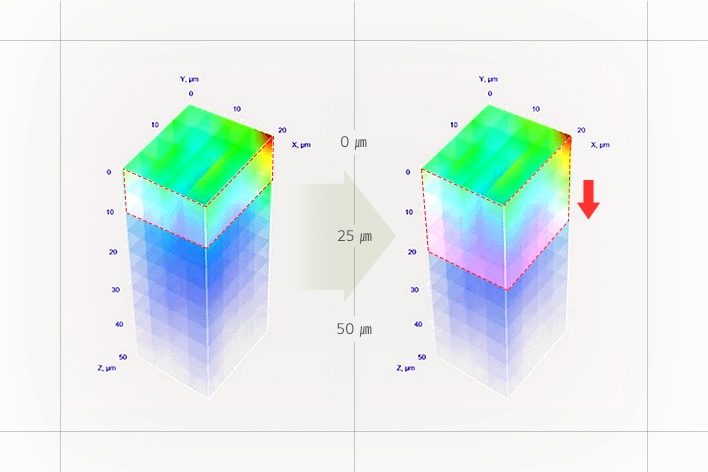

3) Excellent absorbency

-Skin Booster Boosting Mode in level 6 for 3 minutes

-Human application test results: Use of TOXNFILL Hyaluronic Boosting Ampoule / Comparison between two control groups, Skin Booster + Cosmetics vs. Hand + Cosmetics /

After absorption of the ampoule and a 30-minute wait, the degree of absorption, absorption amount, absorption depth, and absorption speed of the ampoule were measured using Raman microscopy, and the improvement rate compared to the Hand + Cosmetics control group was expressed in a %.

-February 5 - February 16, 2024 / 20 adult women (including 10 with sensitive skin) / P&K Skin Clinical Research Center

-Test results have been excerpted from the test performance report for consumer understanding.

-There may be personal differences depending on individual skin characteristics or skincare product combinations.